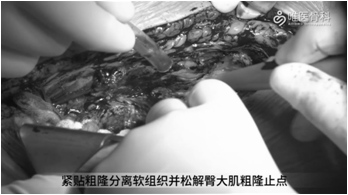

手术显露:沿原切口逐层切开,然后紧贴粗隆分离软组织,并松解臀大肌粗隆止点。切开关节囊,留取关节液培养,关节液检查内容包括关节液常规(白细胞计数、分类)、白细胞酯酶试纸检测,微生物培养(需氧和厌氧)。

切除瘢痕组织:削薄并切除假体周围多余的瘢痕组织,常规行髋关节后脱位,并给予剥离股方肌与股外侧肌,去除围绕在假体与骨周围的瘢痕。